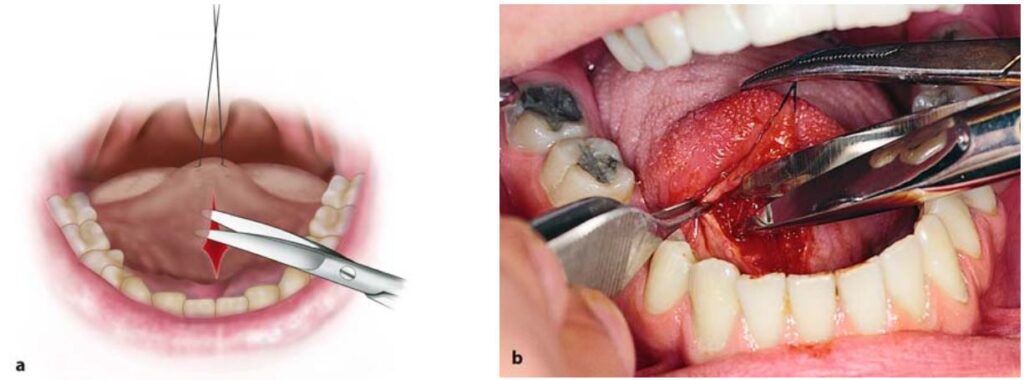

Dùng kéo tỉa mô làm giảm căng mô xung quanh bờ tổn thương rồi khâu lại (H10.86 – 10.88).

Do thắng lưỡi luôn nằm gần với các tĩnh mạch lưỡi và ống dẫn tuyến dưới hàm nên khi phẫu thuật phải hết sức cẩn thận.